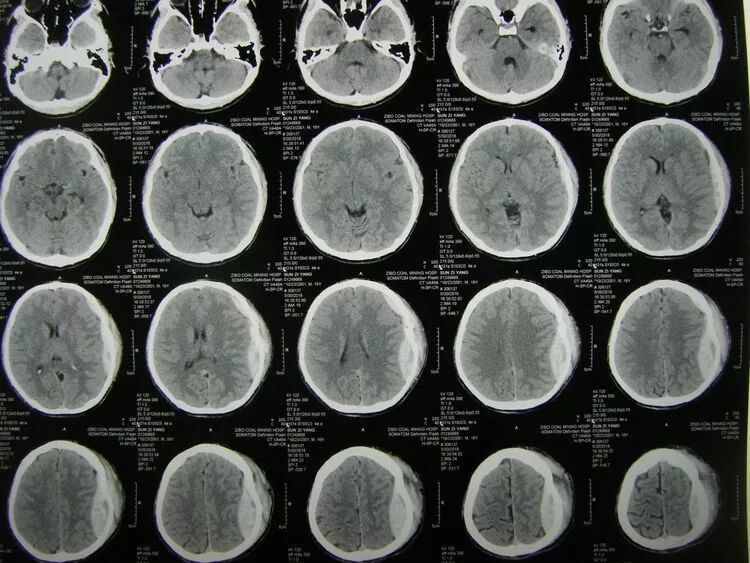

患儿男,16岁,头部等处车祸伤2小时入院,嗜睡状,左额颞顶处有数处头皮创口,颞顶处创口可见骨折内陷。

CT示:

额颞顶部硬膜外血肿,占位效应明显,局部颅骨粉碎骨折并内陷。

骨窗片显示额颞顶交界区骨折内陷并粉碎。